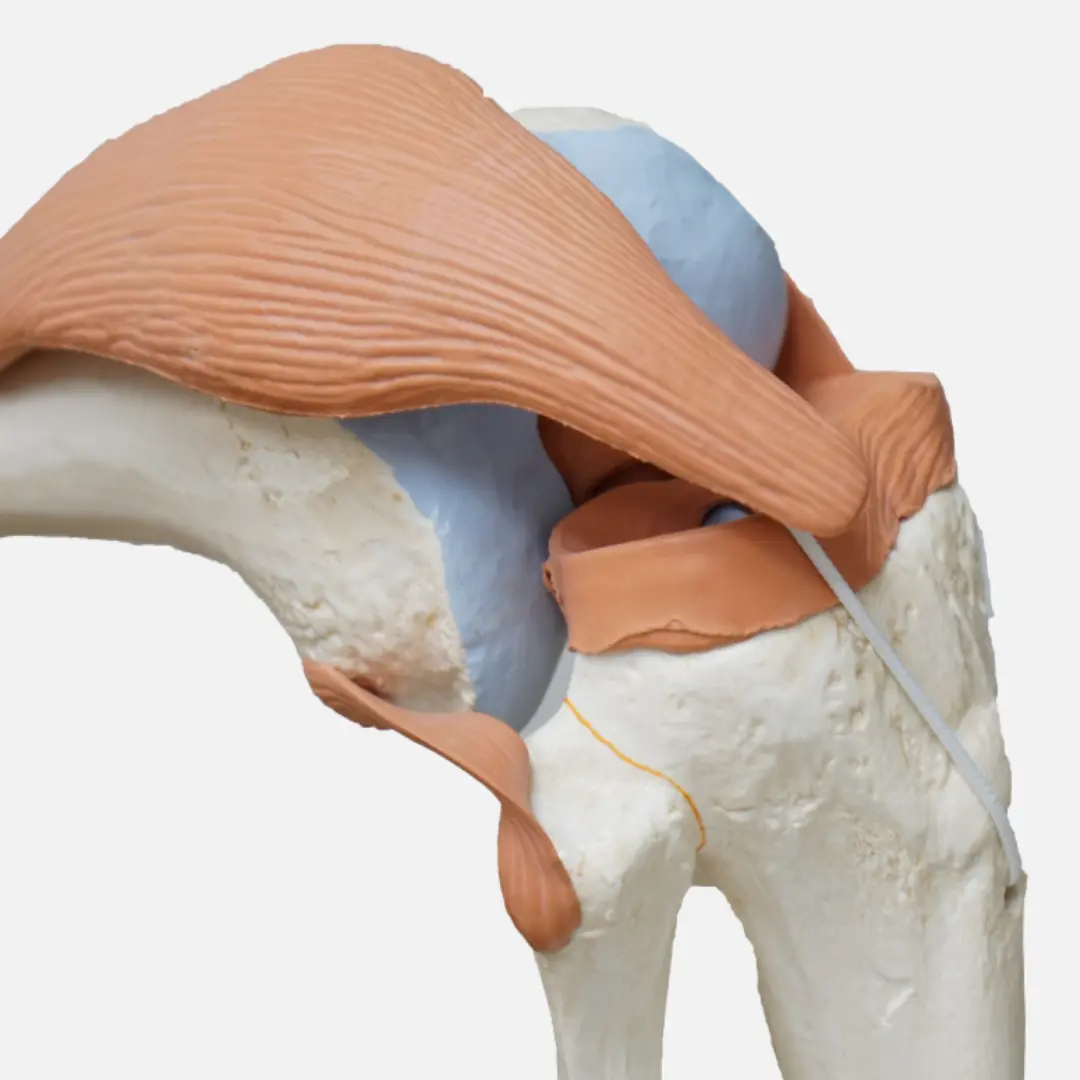

- 연골 보호 및 강화: 브로콜리, 등푸른 생선, 견과류, 뼈 국물 등에 풍부한 영양소들은 무릎 관절의 핵심인 연골을 보호하고 손상을 예방하며, 더 나아가 연골을 강화하는 데 도움을 줄 수 있습니다. 마치 건물의 뼈대처럼, 튼튼한 연골은 무릎 관절의 안정성을 높여줍니다.

- 무릎 부상 경험자: 과거 무릎 부상을 경험했거나 현재 재활 치료 중인 분들은 연골 재생 및 관절 조직 회복에 도움이 되는 음식을 섭취하여 빠른 회복과 재발 방지에 힘써야 합니다. 마치 건축 자재처럼, 손상된 부위를 튼튼하게 재건하는 데 필수적인 영양소를 공급합니다.